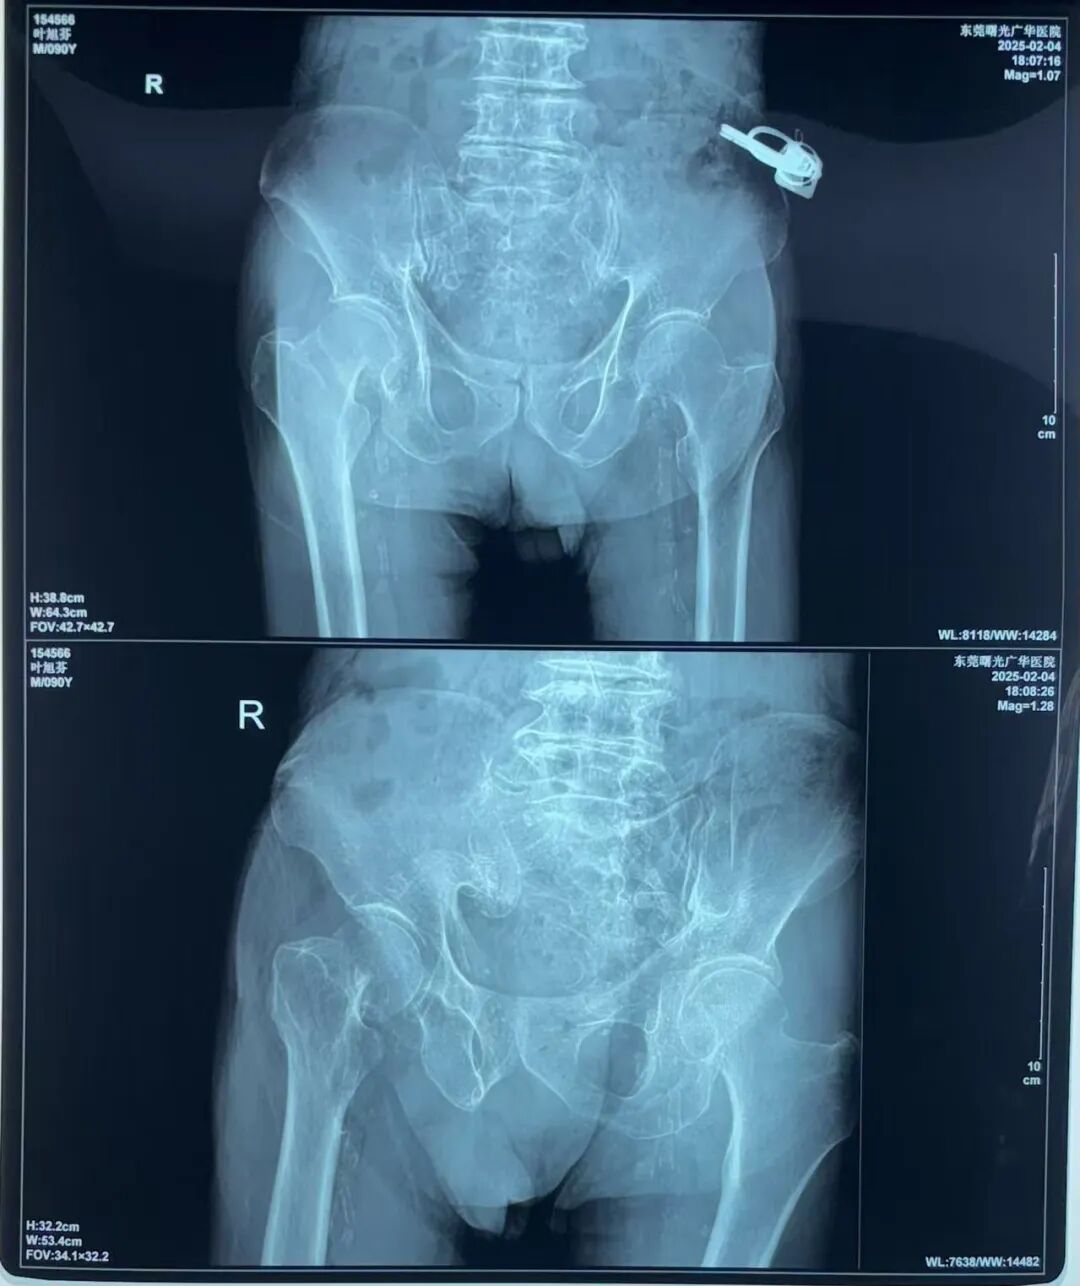

95岁的患者叶老先生,因不慎跌倒导致右股骨颈骨折,同时伴有肺支气管扩张感染、白内障、脑萎缩等十余项基础疾病,身体状况极为复杂。面对高龄患者的治疗风险,我院外一科(骨科)迅速启动多学科协作机制,联合麻醉科、呼吸内科、心血管科等专家团队进行术前综合评估,制定个性化手术方案。在严密控制基础疾病后,团队凭借丰富的经验和精湛的技术,成功为患者实施右侧髋关节置换术,手术全程仅耗时1小时,术中出血量低至100ml,最大程度降低了对患者身体的负担。

影像检查